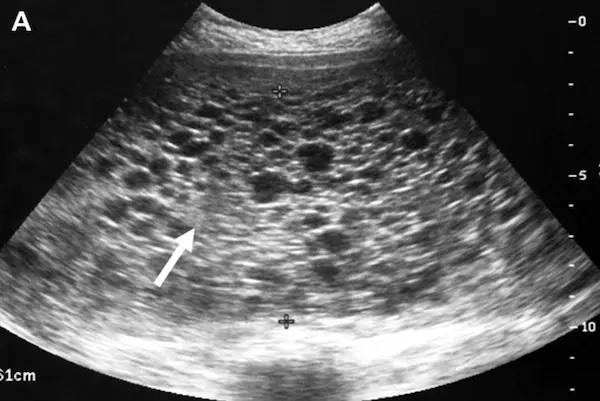

- الفحص بالموجات فوق الصوتية (السونار): يعتبر الطريقة الرئيسية لتشخيص الحمل العنقودي، حيث يظهر عبر الفحص عبر المهبل أو البطن مجموعة من الحويصلات داخل الرحم تشبه عناقيد العنب، وغالبًا لا يرى جنين أو كيس للسائل الأمنيوسي.